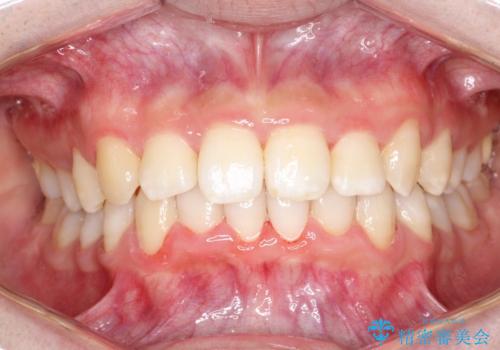

重度のガタガタのインビザラインによる非抜歯矯正

ガタガタの度合いが大きかったので少し時間がかかりましたが、非常に協力的な患者様でしたので、抜歯をせず計画通りに治療を終えることができました。

- 2年2ヶ月